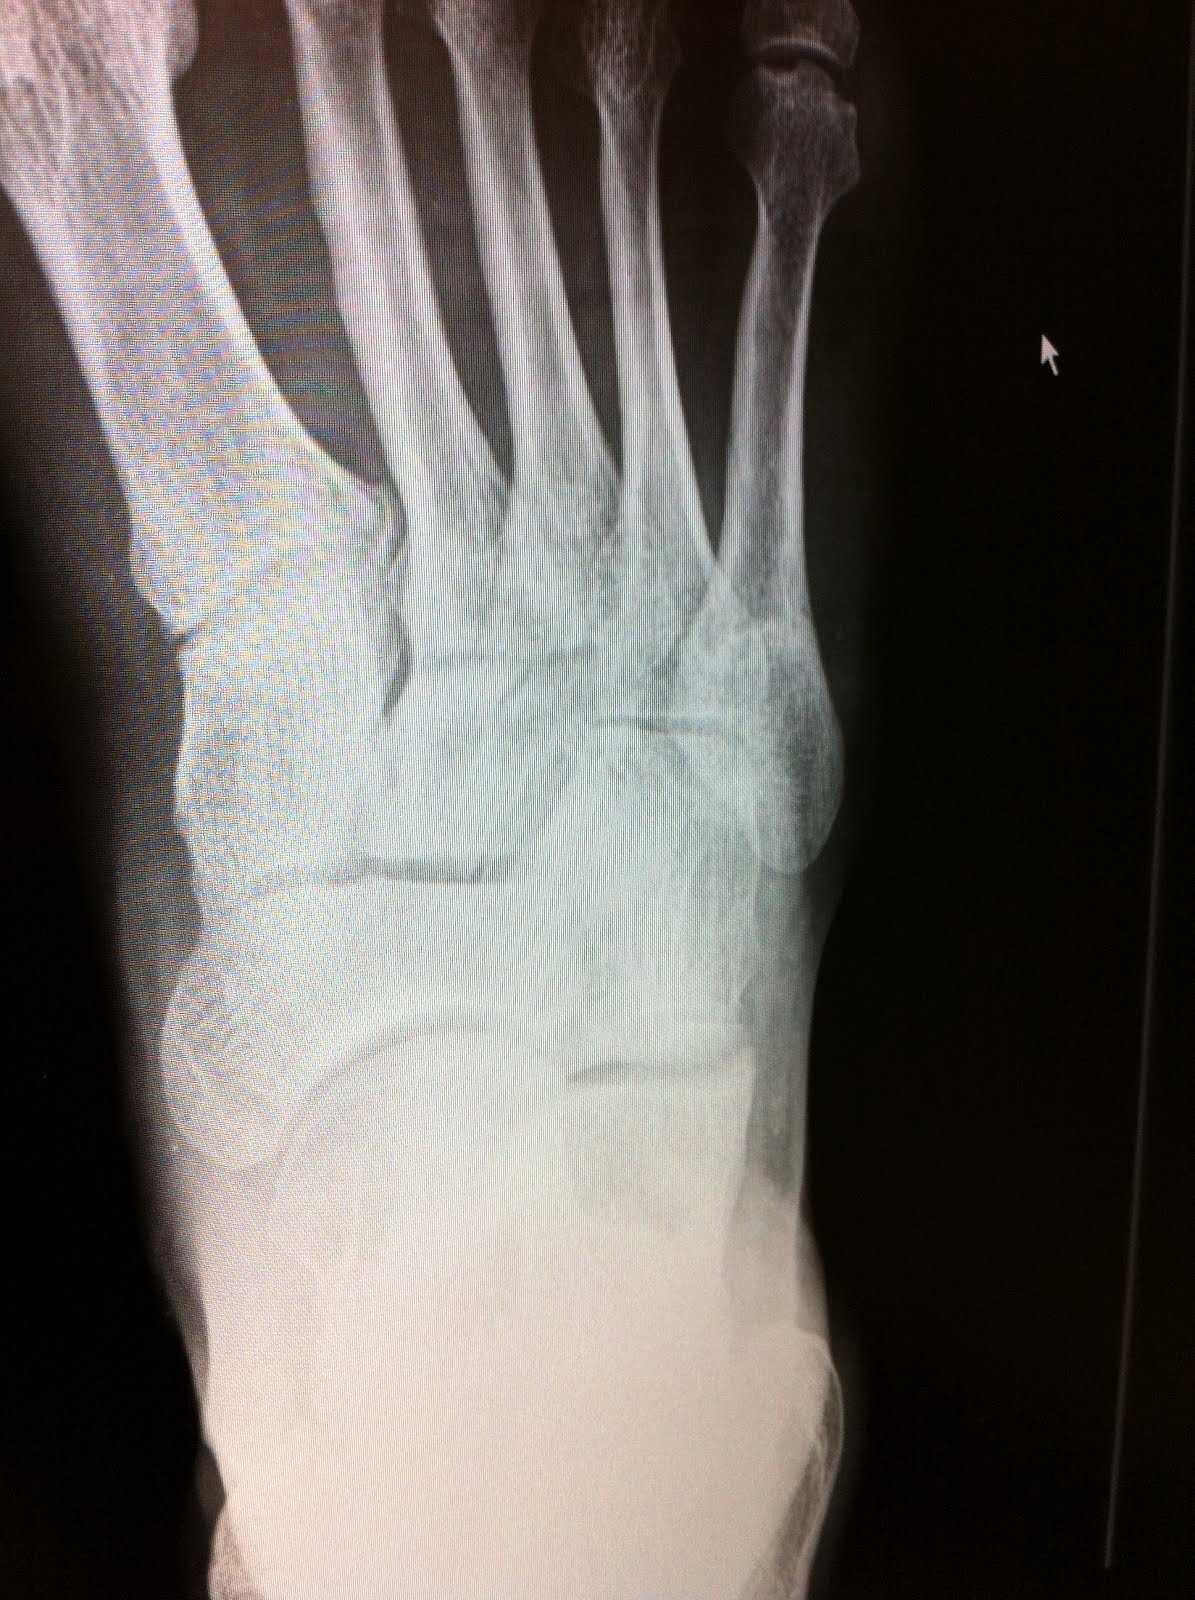

Back to the point. Last summer after snapping my 5th metatarsal for the second time in mere months I had a follow up xray six weeks out that could not have been any worse. Here's the evidence of just how bad that was. A month and a half after breaking my foot and it had actually gotten worse, not better.

Late June 11 - 6 weeks out

This brings me to my point...I had one for once. I had a life saving moment in which I got educated on, and into contact with a brand/device called the Orthofix Bone Stimulator. I had a non-union fracture and both sides of that fracture were still quite angry with each other. Neither side had apologized and both were still blaming the other for the second such break...when in fact it was pretty much all my minds fault for telling my foot it was healthy enough and had to do 100mile training weeks just a few months off crutches. See how I effectively removed the blame of myself and segmented it into parts of my own body. My hands are clean here.